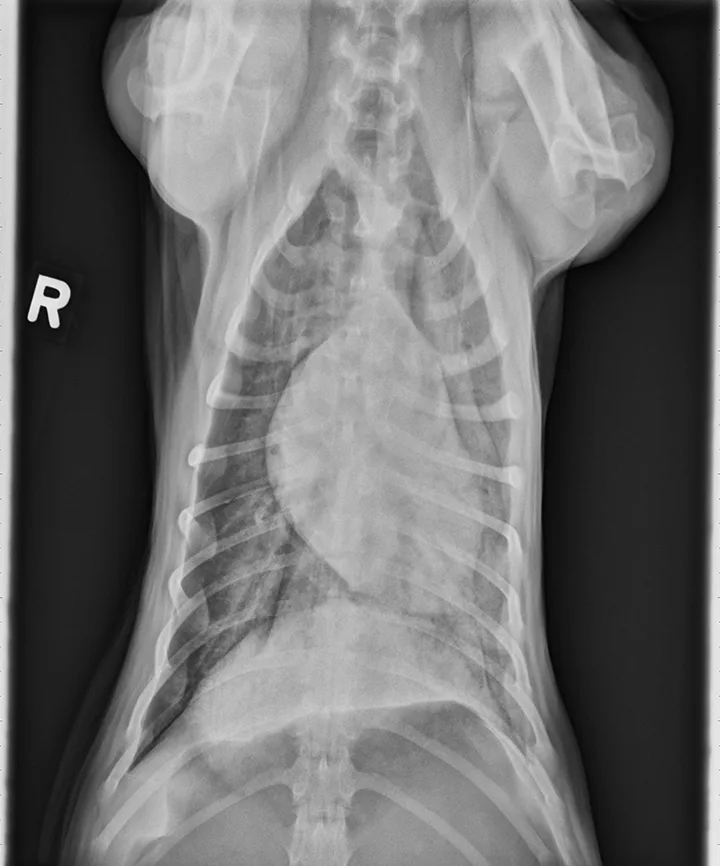

Thoracic radiographs can appear normal initially, but changes to the pulmonary parenchyma may become more apparent within 24 to 72 hours as respiratory injury progresses. Evidence of patchy pulmonary edema with bronchial, interstitial, or alveolar patterns may be observed [Figures 1 and 2].6,13,16,19 Right middle lung lobe consolidation and pleural effusion in cats have been reported.6,13,16 An alveolar pattern may be seen on serial radiographs in patients that develop secondary bacterial pneumonia.6

VD thoracic x-ray of dog showing opacity of lung parenchyma concentrated in caudal fields and overlapping cardiac silhouette.

FIGURE 2

A severe, patchy interstitial-to-alveolar pattern, more severe in the left hemithorax and caudodorsal lung fields, in a dog with smoke inhalation injury after a house fire